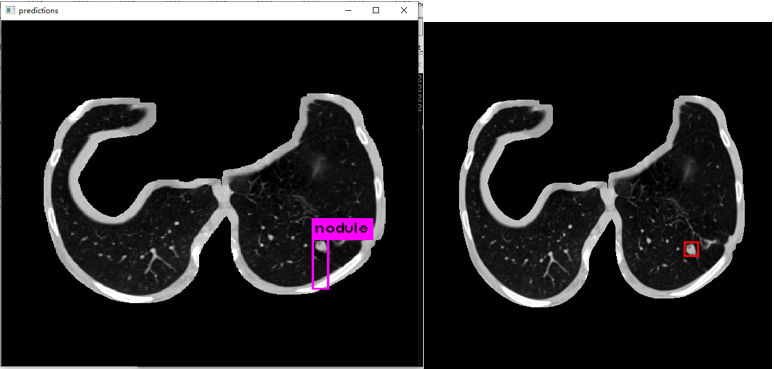

更新:2019.9.14

使用分割后的数据进行训练

经过大约四天的训练后确实比之前有了显著提升

下图左边是预测,右边是根据标注生成的ground truth。